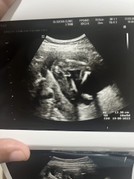

วันนี้โชว์แบบไม่อายเลยจ้ามาทั้งพวงเลยทีมสิงหาลูกชายค่ะ

ของแม่ๆชายหรือหญิงค่ะ

19 สิงหา กลีบชัดมากแม่ 55

27 สิงหา ทีมลูกชายค่าา

8สิงหาคม ผู้หญิงค่ะ🥰

29 สิงหา โชว์ไข่ไปเลยจ้า

7สิงหา ผู้หญิงจ้าาาา

11สิงหา ลูกสาวค่าาา🥰

โชว์จู๋ครับ25สิงหา

9สิงหา ผู้ชายครับ

17 สิงหาผู้ชายค่ะ

23สิงหา ชายค้าบบบ